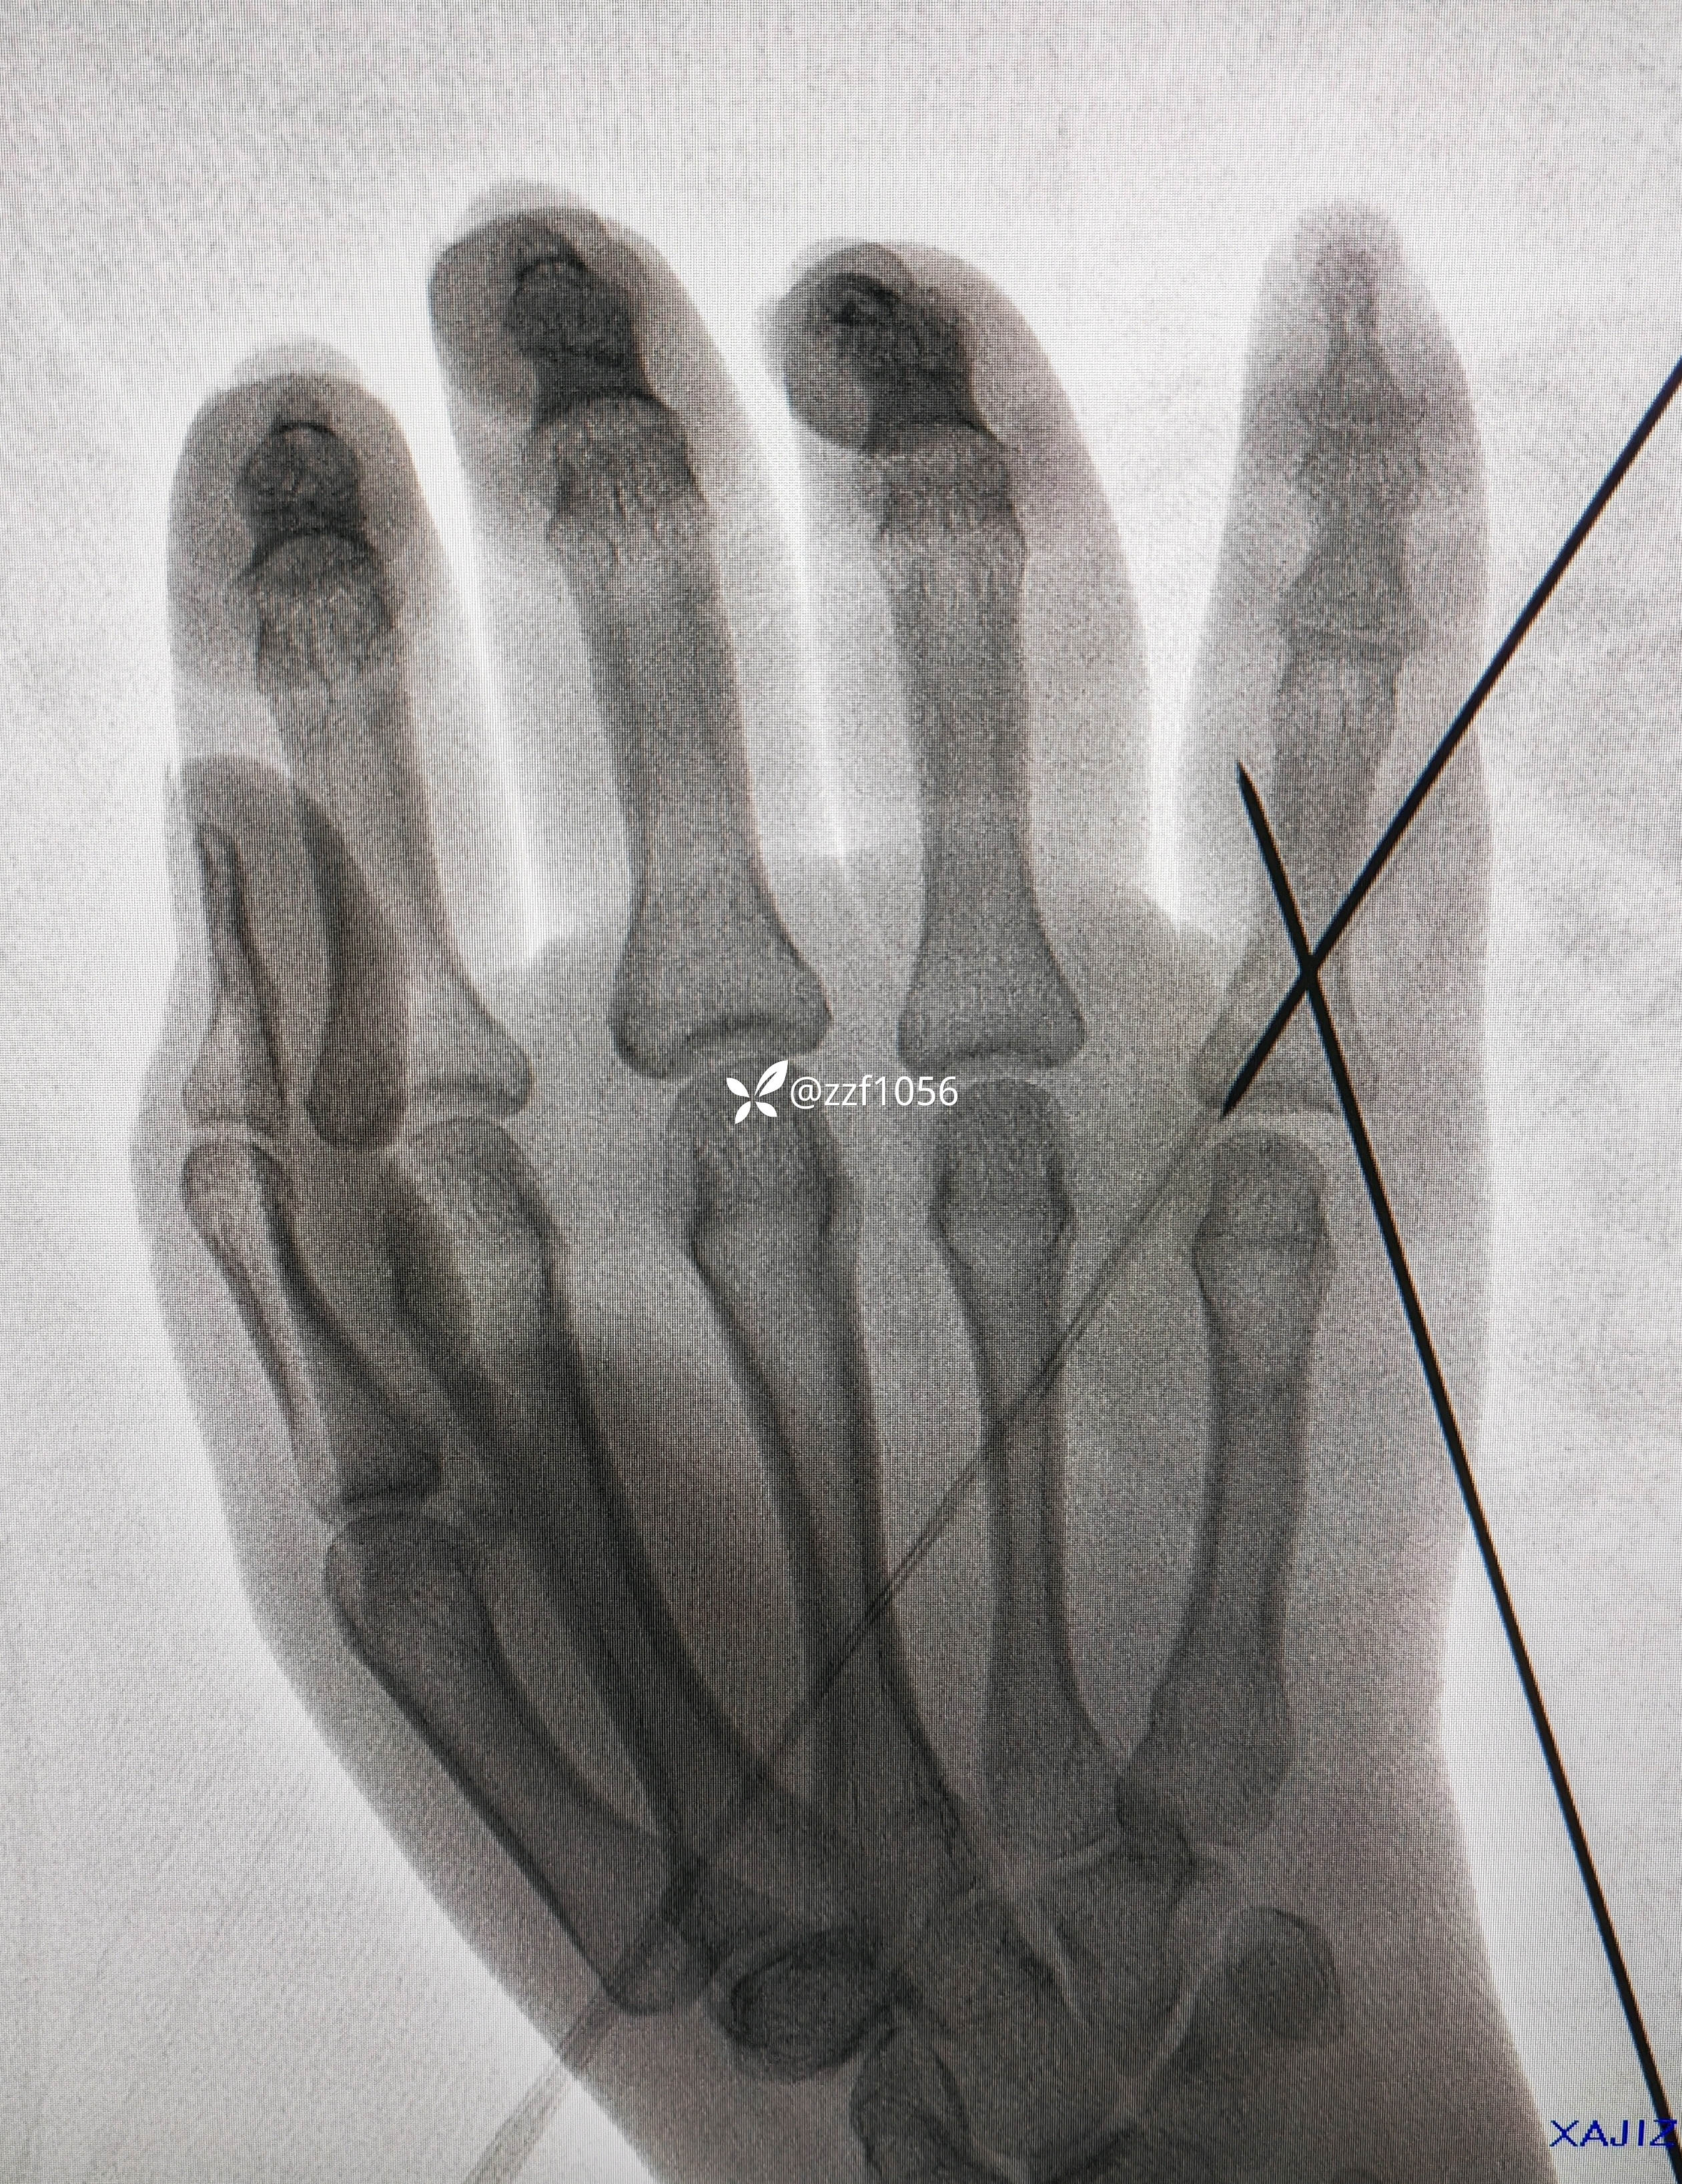

15:10分消毒铺巾准备台上行腕部神经阻滞麻醉,手法整复直接经皮交叉穿针,术中透视并调整,处理针尾,术中活动良好克氏针稳定;

看看术中效果

15:30走出手术室返回病房。